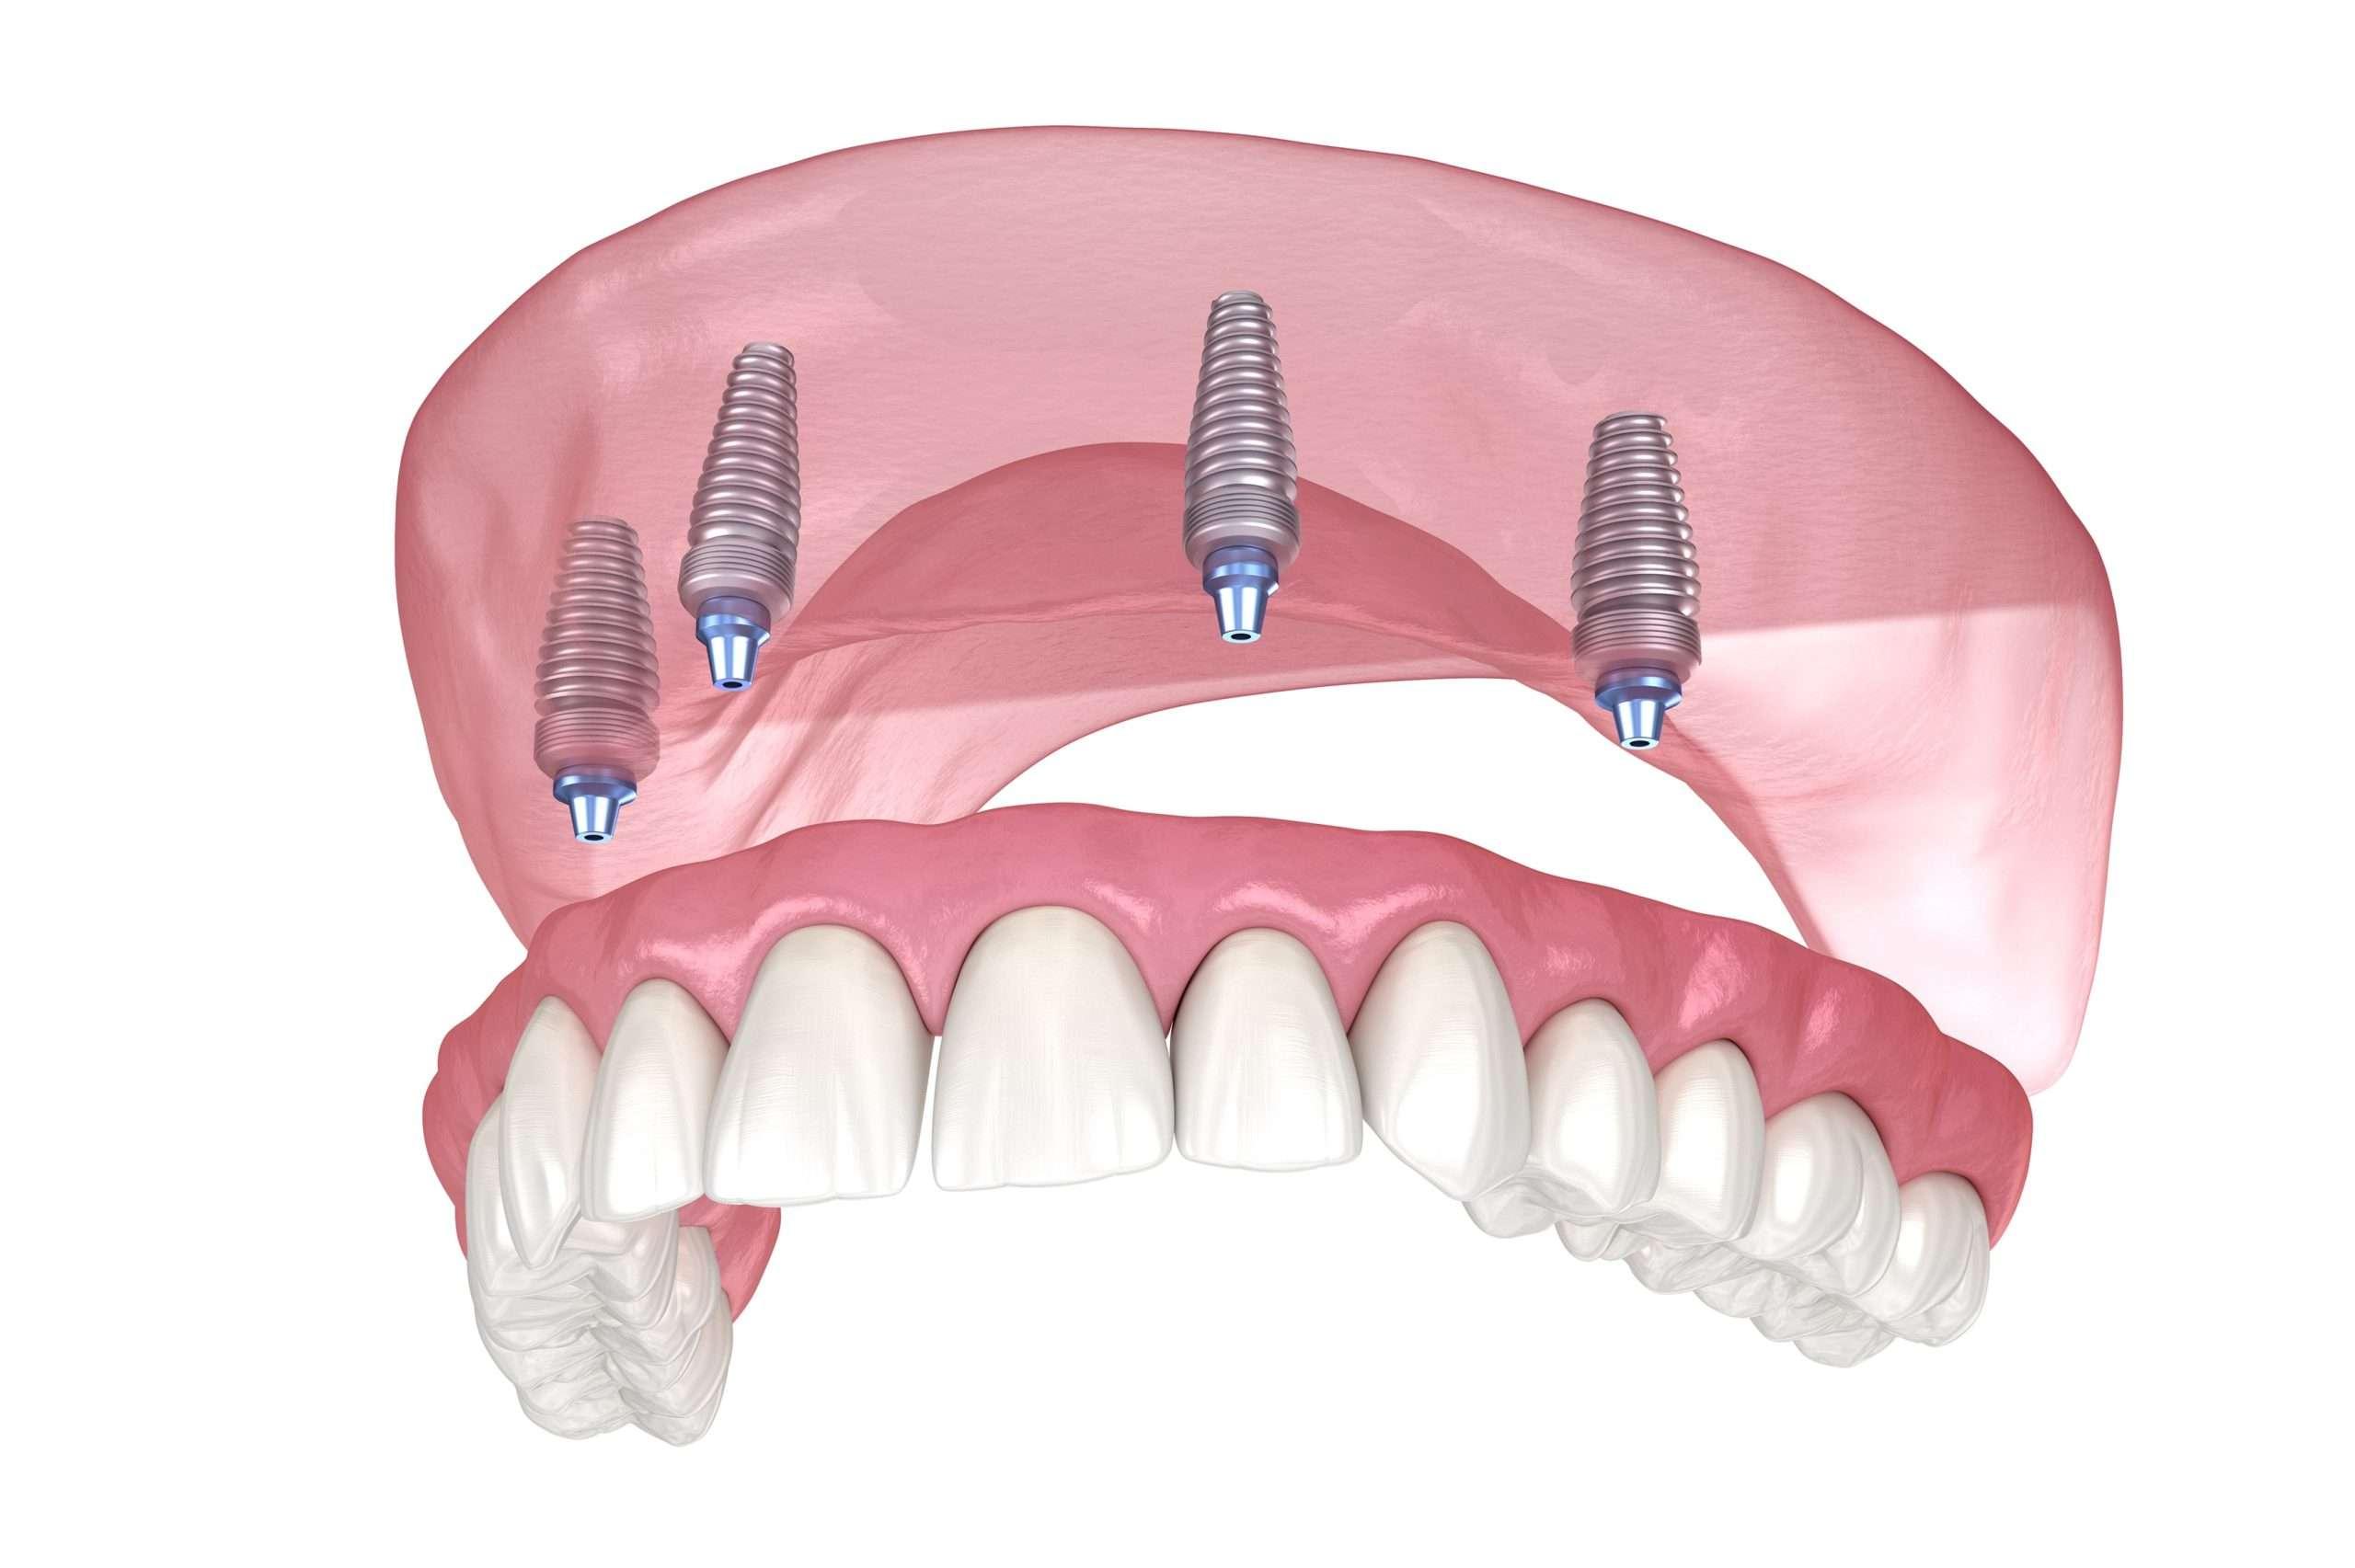

Durable Solutions Like Dental Implants

Losing a tooth doesn't have to be permanent. dental implants Oldham provide a strong, natural-looking replacement that functions like a real tooth. It's a long-term fix that active suits, busy lifestyles.

Comfortable Dental Implants

Older patients benefit greatly from dental implants that restore chewing ability and confidence. With high success rates, they're a reliable choice for those looking to maintain independence and oral function.

Are dental implants safe?

Absolutely. Most patients report minimal pain, and implants have success rates over 95%.